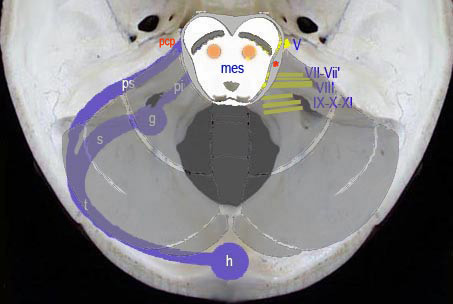

Outre le cervelet, cette loge est occupe par le segment bulbo-protubrantiel du tronc crbral & par les deux espaces ou angles ponto-crbelleux quÕils dlimitent entre eux.

LÕangle ponto-crbelleux est un espace paramdian exigu & profond, dlimit de chaque ct par la protubrance reprsente principalement par le PCM, la partie rostrale de la face latrale du bulbe, & par la face ventrale de lÕhmisphre crbelleux.

Sch.31 Š Aspect ventral

Il est occup par le prolongement latral de la citerne pontique, par le flocculus qui masque le plexus chorode latral du 4” ventricule, par de nombreux nerfs & par des vaisseaux crbelleux. CÕest ce niveau que se dveloppent les tumeurs de la VIII” paire

(neurinomes de lÕacoustique).

Les troncs nerveux ont une disposition cardinale : trs en dedans le VI, en haut le trijumeau, en dehors le faisceau acoustico-facial dirig vers le pore auditif interne, &

en bas le groupe des nerfs mixtes (IX-X-XI) orients vers le trou dchir postrieur.

Les troncs nerveux issus du tronc crbral (pont & bulbe) sont tags de haut en bas :

V : les deux branches du Trijumeau

VI : nerf oculaire externe

VII & VIIÕ : nerfs Facial & Accessoire

VIII : nerf Auditif (acoustico-vestibulaire)

IX : Glossopharyngien

X : Pneumogastrique

XI : Spinal bulbaire

Sch.33

Les troncs nerveux en rapport avec lÕespace ponto-crbelleux sont issus des tages pontique & bulbaire du tronc crbral. Leur disposition spatiale est grossirement cardinale :

- en haut, le nerf trijumeau se dirige vers le ganglion de Gasser relais ganglionnaire de sa

racine sensitive ;

- en bas, les trois nerfs mixtes (IX, X, XI) orients vers le trou dchir postrieur ;

- plus en dedans, le VI ,

- en dehors, trois autres nerfs : le facial, le nerf de Wrisberg & le nerf acoustico-vestibulaire

orients vers foramen auditif interne. Ils constituent le principal constituant de cet espace.

Sch.34